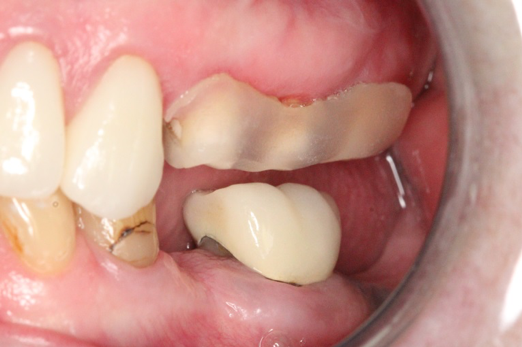

Fig 11. Preoperative healed sites.

Figure 11

Figure 10 through Figure 13 show the preoperative x-ray and the sequence of beginning with healed sites through the surgical placement of the implants. The implants were protected by an Essix-style wound-protection removable retainer for approximately 12 weeks. After the integration phase, the implants and the natural dentition were prepared using traditional crown-and-bridge high-speed diamond and zirconia cutting burs to remove decay and existing restorative materials, to complete and refine the natural-tooth structures to receive full-crown coverage, and to prepare and refine gingival margins of the zirconia implants where needed.